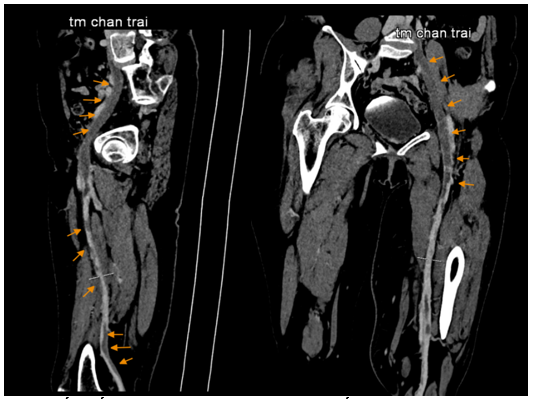

Hình 5: Hội chứng May – Thurner (tĩnh mạch chậu chung trái bị chèn ép bởi động mạch chậu chung phải và cột sống)

Hình 6: Huyết khối tĩnh mạch chân trái trên chụp cắt lớp vi tính

Hình 3: ECG ghi nhận nhịp xoang 73 lần/phút

Xét nghiệm huyết học và sinh hóa trong giới hạn bình thường: WBC = 8,3k/uL, RBC = 5.1 M/uL, PLT = 233 k/uL, creatinin = 91,6 umol/L. Xét nghiệm đông cầm máu trong giới hạn bình thường với: PT = 13s (104%), aPTT = 26s , INR = 1. Do tình trạng huyết khối chỉ xảy ra ở chân trái, kèm bệnh nhân không có yếu tố nguy cơ gợi ý tăng đông, nên gợi ý nhiều đến hội chứng May – Thurner. Bệnh nhân được chụp CT tĩnh mạch chi dưới gợi ý đến hội chứng này. Kết quả CT như sau: tĩnh mạch chậu chung trái bị chèn ép bởi động mạch chậu chung phải và cột sống, đường kính tại gốc d # 2.3mm -> nghĩ hội chứng May – Thurner. Huyết khối cấp/ bán cấp gây tắc hoàn toàn hệ tĩnh mạch chậu trái. Huyết khối giai đoạn cấp/ bán cấp bán phần hệ tĩnh mạch đùi, khoeo và đoạn gần tĩnh mạch sâu cẳng chân trái. Huyết khối gần hoàn toàn tĩnh mạch cơ bụng chân trái. Huyết khối bán phần tĩnh mạch hiển bé.